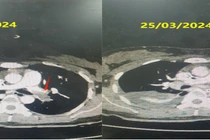

Ngừng tuần hoàn hô hấp do thuyên tắc phổi cấp nguy cơ cao dẫn tới tử vong ngay lập tức nếu không được xử trí kịp thời.